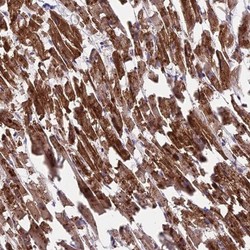

Immunohistochemistry

NBP1-92061 IHC